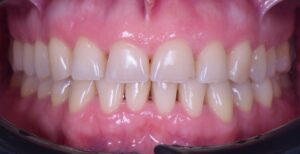

Il segreto della “invisibilità” dei nostri restauri risiede nella sinergia tra la progettazione digitale e la scelta dei materiali.:

- Integrazione marginale perfetta: grazie alla precisione millimetrica della nostra mascherina trasparente, la transizione tra dente naturale e restauro è impercettibile, eliminando l’antiestetico “effetto scalino”.

- Morfologia naturale: ogni dettaglio del wax-up, dalle creste marginali alle micro-tessiture superficiali, viene trasferito fedelmente in bocca.